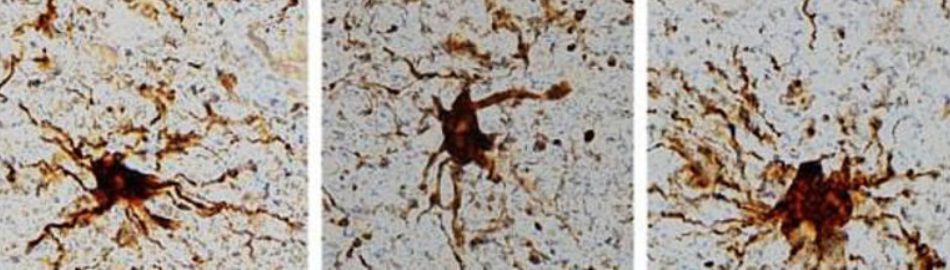

Yukarıdaki araştırmalarla, insan beynindeki bazı hücrelerin ölümden sonra aktivitelerini arttığı belirlendi.Bu zombi genlerinin,

"Glia" adı verilen sinir hücrelerini sarmaktan ve onlara besin ve oksijen sağlamaktan sorumlu olan tek bir hücre tipine özgü olduğu anlaşıldı. Sinir hücrelerindeki düşünme ve diğer aktiviteleri etkileyen başka bir gen grubu, ölümden hemen sonra bozuldu.

Sinir hücrelerindeki genler azaldığında, üçüncü gen grubu aktivitelerini artırdı. Ölümden sonraki değişimin yaklaşık 12 saatte zirve yaptığı belirlendi. Bilim insanları ölseler bile bu hücrelerin büyümeye devam edeceğini ifade ettiler.